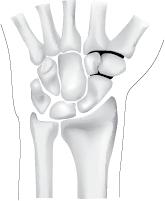

De Plastisch Chirurg maakt een gebogen snee over het polsgewricht aan de kant van de duim. Daarna verwijdert hij het versleten kraakbeen van de (drie) gewrichten. De botjes worden vervolgens met pennen of nietjes aan elkaar gezet (zie tekening). Deze nietjes moet de plastisch chirurg eventueel naderhand weer verwijderen. Soms is extra botweefsel afkomstig van de onderarm of bekkenkam nodig om de botjes beter te laten vastgroeien. Hierna wordt de wond gehecht en een spalk aangelegd voor 4 weken.